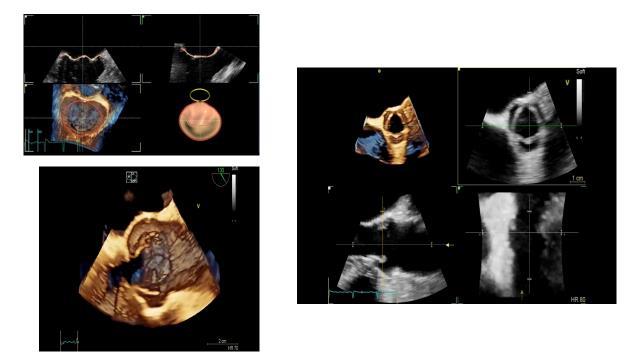

قام المستشفى التخصصي بإدخال تقنية جديدة و متطورة والأحدث عالمياً (GE Vivid   S70 4D System) لتصوير صدى القلب وتصوير القلب عن طريق المريء بتقنية التصوير رباعي الأبعاد.

حيث يعتبر الجهاز من أحدث وأعلى الأجهزة حيث يحتوي على العديد من المواصفات والتكنولوجيا الحديثة والفريدة مثل C- Sound Technology  التي تنعكس في الحصول على صور ذات جودة ووضوح عاليتين كما يمتاز نظام 4D TEE في الحصول على صور دقيقة وعالية الوضوح للكشف على أمراض ومشاكل صمامات القلب كما يحتوي على ميزات فريدة اخرى مثل AFI، AEF والتي تزود الطبيب بأدوات لتقييم وظائف القلب بدقة وبذلك يكون المستشفى التخصصي أول مستشفى يقتني هذا الإصدار من الجهاز في الأردن.